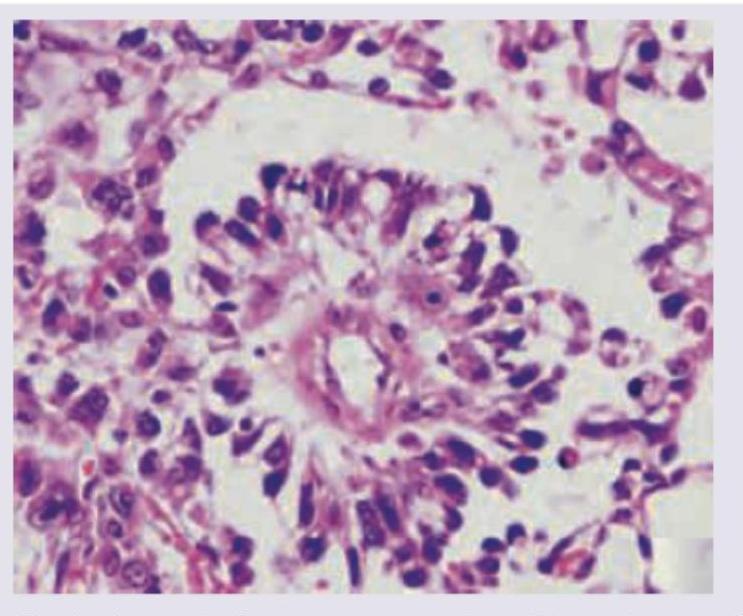

Explanation: ***Endodermal sinus tumour*** - The image displays characteristic **Schiller-Duval bodies**, which are pathognomonic for endodermal sinus tumors (also known as yolk sac tumors). These structures resemble primitive glomeruli with a central vessel surrounded by tumor cells. - Endodermal sinus tumors are aggressive **germ cell tumors** and are common in adolescent girls, often presenting with a large pelvic mass and elevated **alpha-fetoprotein (AFP)**, correlating with the clinical picture. *Granulosa cell tumour* - Granulosa cell tumors are **sex cord-stromal tumors** and typically present with features of estrogen excess, such as precocious puberty or abnormal uterine bleeding. - Histologically, they are characterized by **Call-Exner bodies**, which are small, gland-like structures containing eosinophilic fluid, not seen in the provided image. *Arrhenoblastoma* - Arrhenoblastomas (Sertoli-Leydig cell tumors) are also **sex cord-stromal tumors** that typically cause virilization due to androgen production. - Histologically, they show cords and tubules composed of Sertoli and Leydig cells, which are distinct from the structures in the image. *Thecoma* - Thecomas are benign **sex cord-stromal tumors** primarily composed of lipid-rich stromal cells, often producing estrogen. - They typically appear as solid, yellow tumors and histologically consist of spindle cells with intracellular lipid droplets, without the complex architectural patterns like Schiller-Duval bodies.